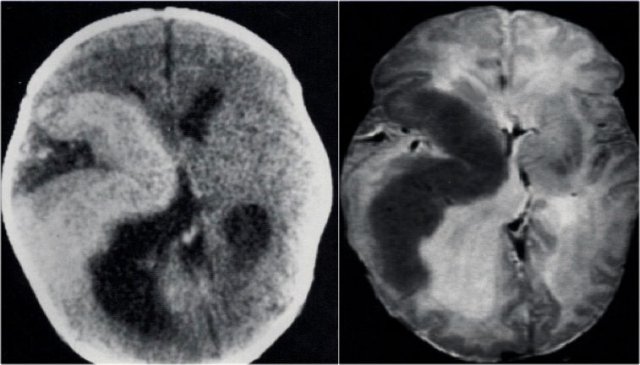

CT and T2WI in a patient with a right hemimegalencephaly.

There is dysplastic thick cortex and ventricular dilatation on the affected side.

Rasmussen's encephalitis is a progressive hemispheric atrophy of unknown origin.

Patient develop an increasing frequency of seizures and progressive hemiplegia.

Notice that, opposed to hemimegalencephaly, the smaller hemisphere is the site of abnormality, and the lateral ventricle is larger in the smaller hemisphere.